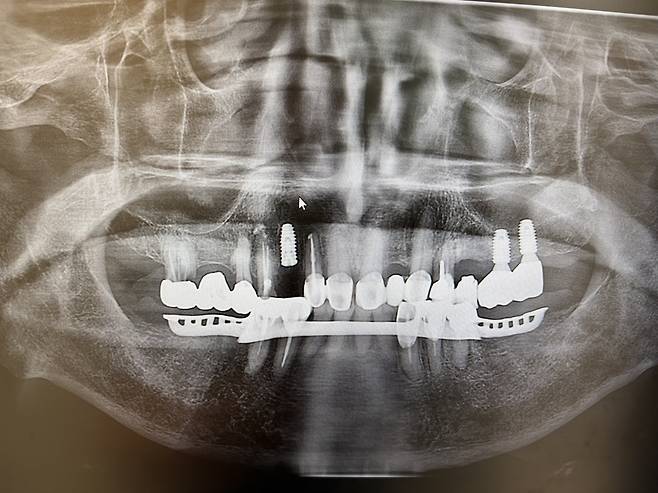

| ▲ 아버지의 임플란트 영상사진, 왼쪽에 윗니부분에 선명한 것이 임플란트 |

| ⓒ 이혁진 |

2주 후 다시 치과를 방문했다. 임플란트 이후 잇몸 상태와 염증 등 부작용을 체크했다. 여기서도 좋은 결과를 얻었다. 심은 나사를 엑스레이로 확인해보니 잘 뿌리내리고 있었다. 이제는 3개월 후 임플란트 상황을 더 지켜보고 괜찮으면 나사 위에 치아를 덮는 소위 '크라운' 보철만 남았다.